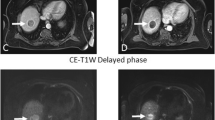

Figure 1 shows pretreatment quantitative MR images for a patient with tumor response and a patient without response to TACE, respectively. There were no significant differences in gender, involved lobe of the liver, ADC, and pre-TACE tumor size between response and nonresponse group (All p values ≥ 0.05). However, age > 60 (p value = 0.018) had a significant difference between two groups. D of tumor tissue in response group ([− 1.45 ± 4.87] × 10 − 3 mm2/s) was significantly higher than nonresponse group ([− 7.38 ± 4.96] × 10 − 3 mm2/s) (p value = 0.005). D* of tumor tissue in response group ([− 1.51 ± 4.83] × 10 − 3 mm2/s) was also significantly higher than nonresponse group ([− 7.41 ± 4.91 × 10 − 3 mm2/s]) (p value = 0.005). Meanwhile, f value of HCC tumor was significantly higher in response group ([0.51 ± 6]) than nonresponse group ([− 6.9 ± 5.89]) (p value = 0.004*) (Table 2).

Pretreatment MR images of two patients with responded and nonresponded lesions to TACE. a–d Pretreatment MR Images on the same slice of one lesion in segment eight and right lobe of the liver in a 40-year-old woman who did show tumor response to TACE. a–d IVIM-ADC, D, D*, and f maps, with the arrow showing the HCC lesion on the same slice with mean ADC, D, D*, and f values of 0.92 × 10 − 3 mm2/s, 1.04 × 10 − 3 mm2/s, 0.97 × 10 − 3 mm2/s, and 3.53 × 10 − 3 mm2/s, respectively. e–h Pretreatment MR Images on the same slice of one lesion in segment four and right lobe of the liver in a 40-year-old man who did not show tumor response to TACE. e–h IVIM-ADC, D, D*, f maps, with the arrowhead showing the HCC lesion on the same slice with mean ADC, D, D*, and f values of 0.9 × 10 − 3 mm2/s, 1.23 × 10 − 3 mm2/s, 1.4 × 10 − 3 mm2/s, and 3.9 × 10 − 3 mm2/s, respectively